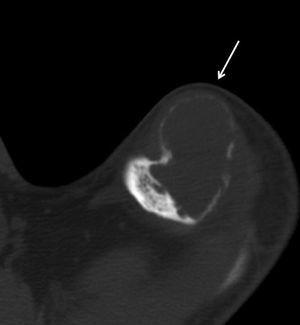

Figura 4. Imagen de tomografía axial computarizada que corresponde a un tumor pardo en la clavícula izquierda